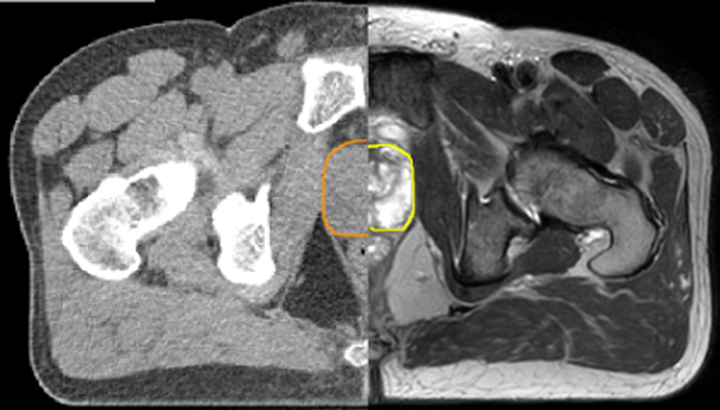

MRIは軟部組織の視覚化に優れており、幅広い画像コントラストに対応します。これにより、MRIは腫瘍の境界をより正確に描出できる強力なツールとなっています。放射線治療プロセスにおいて、標的体積の描出における不確実性が指摘されることがあります**。ターゲットとその近傍のリスク臓器をより良好に可視化することは、標的体積の描出を改善するための重要な因子です。また、MRIの役割は機能的イメージングにより広がりつつあり、ターゲットの評価と治療反応の両方の情報を提供します。

MRIはCTと比較して軟部組織のコントラストに優れているため、腫瘍の境界や近接する重要な構造をより明確に可視化できます。

さまざまなコントラスト情報の利用により、腫瘍の特徴や腫瘍の範囲について有益な情報が得られます。また、追加照射のストラテジーへの情報提供にもなります。

解剖学的情報に加え、MRIは腫瘍の検出と描出、および治療反応のモニタリングに有益な機能的情報提供することができます。

例えば、拡散強調画像(DWI)は腫瘍の水分子の移動(拡散)の制限を示すほか、リンパ節の識別にも用いられます。また、組織や病変部の見かけの拡散係数(ADC)の変化は、放射線治療に対する腫瘍の反応を予測するのに役立つ知見を提供することができます。